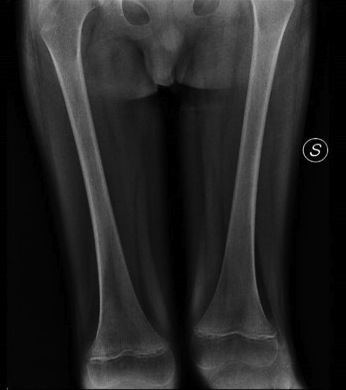

Paziente 3 - Maschio di 7 anni con sindrome genetica (microduplicazione 1q21.1) e rifiuto dell’alimentazione. Presenta improvviso dolore al femore sinistro ed esegue Rx con evidenza di apposizione periostea sul versante laterale e mediale del femore a livello diafisario (Figura 2). La scintigrafia ossea mostra iperattività osteometabolica a livello del femore sinistro e in altre sedi. Per cui, nel sospetto di CRMO esegue RM che conferma la presenza di molteplici aree di alterata intensità di segnale. Si programma quindi biopsia ossea ma il dosaggio della vitamina C permette di porre diagnosi di scorbuto.